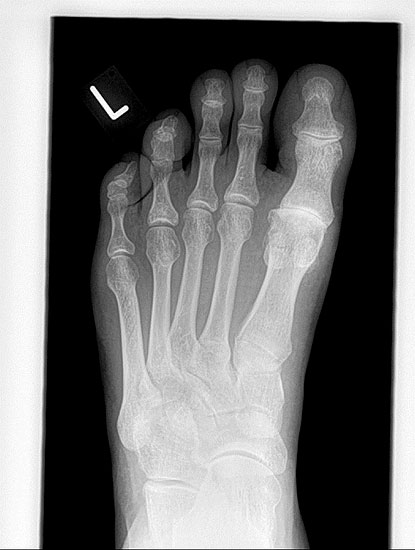

• Röntgenaufnahmen des Vorfußes (unter Belastung) im dorsoplantaren und seitlichen Strahlengang (Abb. 1a+b)

• Beurteilung des Erkankungsstadiums anhand der typischen Arthrosekriterien (Einteilung nach Regnauld) 2

• Beurteilung des Intermetatarsal-Winkels (IMA), des Hallux valgus-Winkels (HVA), mögliche Korrektur der des IMA von 6° durch alleinige Arthrodese, darüber hinaus evtl. zusätzliche MT-I-Korrektur notwendig 101112

• Beurteilung des Metatarsale-Index und der Zehenlänge DI und II, insbesondere nach Voroperationen hinsichtlich einer evtl. notwendigen Verlängerung des ersten Strahls durch Knochenspaninterposition